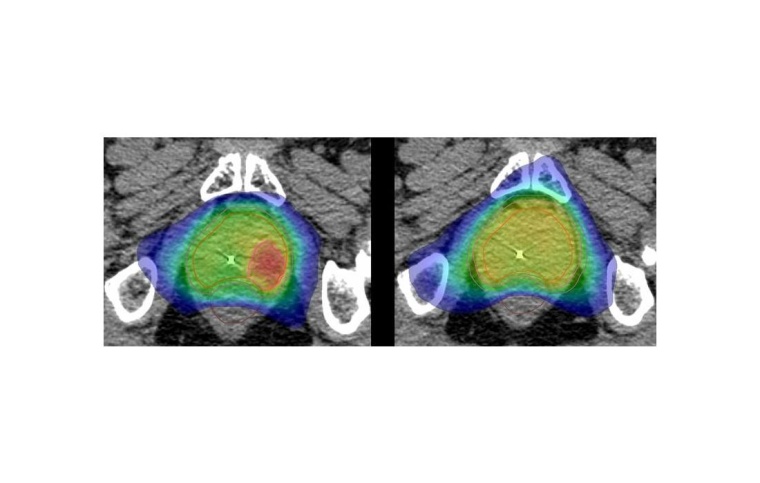

Statt wie bisher die gesamte Prostata gleichmäßig zu bestrahlen, werden im Rahmen der HypoFocal-SBRT-Studie zusätzlich gezielt jene Bereiche des Organs, in denen die hochpräzise Bildgebung den Tumor anzeigt, mit besonderer Intensität bestrahlt. Dadurch soll eine verbesserte, effektivere Therapie und Schonung des umliegenden Gewebes, wie Blase und Darm erreicht werden. Zudem verkürzt sich die Behandlungszeit deutlich.